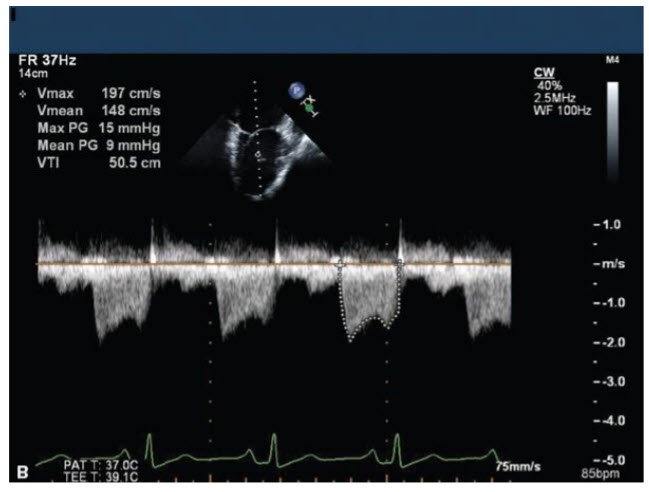

The images in Figure below A–E come from an 18-year-old young man with marked shortness of breath (SOB).

The most appropriate course of action would be

A. Closed mitral commissurotomy because he has a split score of 0 to 4 and minimal mitral regurgitation (MR)

B. Percutaneous mitral valvuloplasty (PMV) because he has a split score of 4 to 8 and minimal MR

C. Surgical MVR because he has a split score of 8 to 12 and minimal MR

D. Surgical MVR because he has a split score of 0 to 4 with significant MR

E. Surgical MVR because he has a split score of 4 to 8 and significant MR